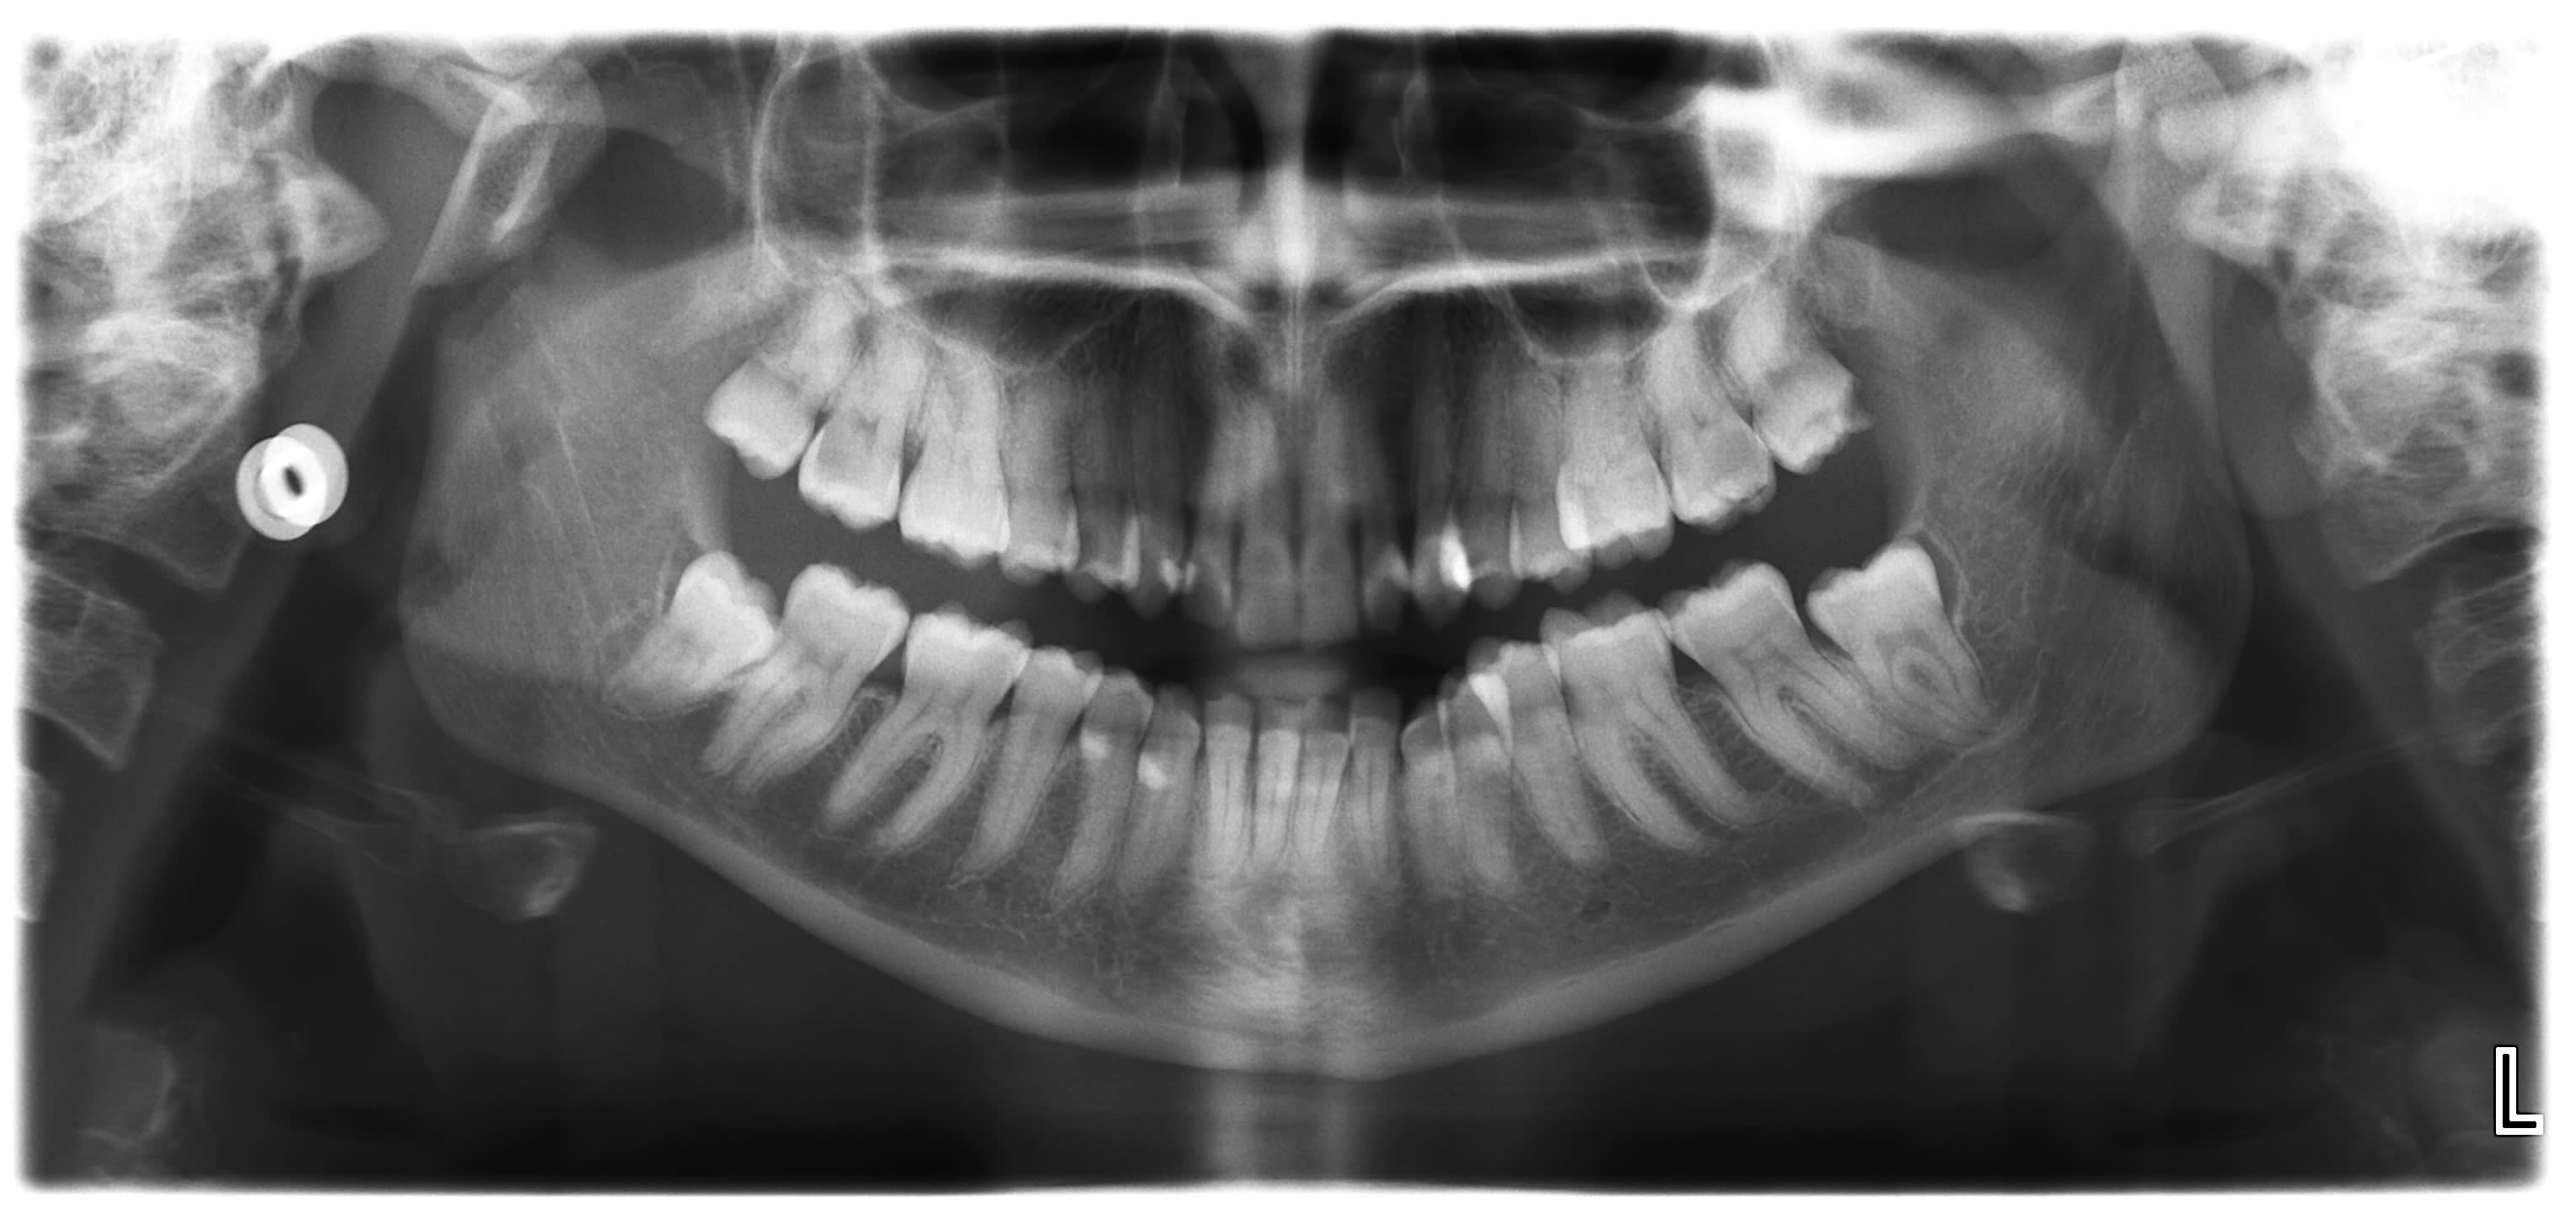

25 ans, crise epilepsie, et boom le condyle droit... Ca fait la troisieme en septembre.

je vois pas le trait de fracture en 43, tu l'a vu ? vous l'avez cherché pendant ? le bloc était mobile ?

Pour la plaque au niveau 43 c pour faire bosser les internes. :0))

Y avait une ligne de fracture superficielle en lingual sur scanner trauma. C est plus prophylactique qu autre chose.